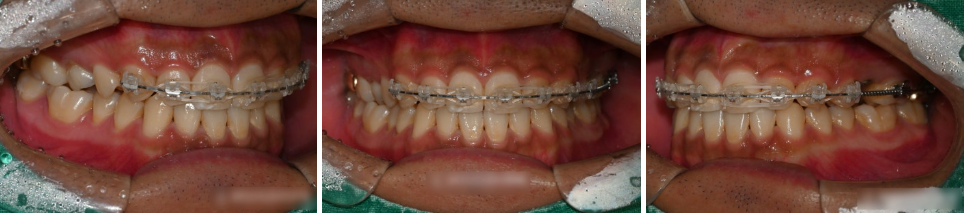

부분 교정을 진행하는 과정에서는

어금니 뿐만 아니라 다소 틀어진 앞니까지

함께 포함하여 이동시켰습니다.

꼭 치료가 필요한 치아들에만 브라켓을 부착하여

불편함을 최소로 하고 배열하던 모습입니다.

상봉동 교정치과 의 치료가 마무리가 되는 시기에

임플란트의 나사를 식립하는

방향으로 치료계획을 세웠습니다.